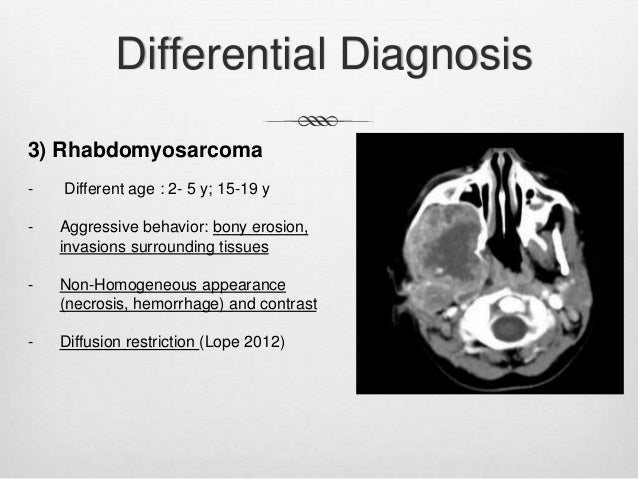

PPT - Pediatric Head And Neck Malignancies PowerPoint Presentation

www.slideserve.com

www.slideserve.com

rhabdomyosarcoma neck presentation pediatric head malignancies ppt powerpoint dna amplification gene cases